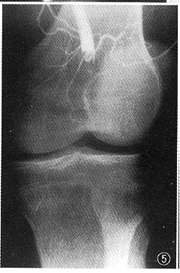

图5,6 男,35岁,左膝部钝性伤6 h,左下肢疼痛。图5为动脉造影,示动脉中断。图6示导管抵近中断处溶栓后远端血流恢复,动脉内充盈缺损,诊断内膜损伤、血栓形成